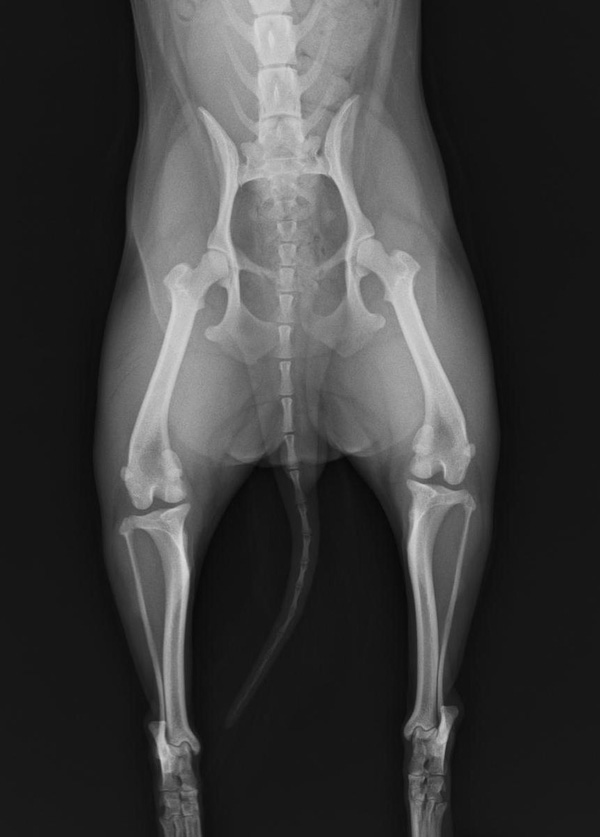

股関節異形成

はじめは、股関節の異常なゆるみに始まり、進行すると骨関節炎を発症します。遺伝性背景があり、昔は、ゴールデン・レトリバーに多く見られましたが、今は少なくなっています。おしりを左右に振って歩く、歩幅が狭い、運動制限によりあまり走ろうとしないなどの症状があります。

小型犬にも似たような病態があります。

レントゲン検査にて、股関節の状態を評価します。